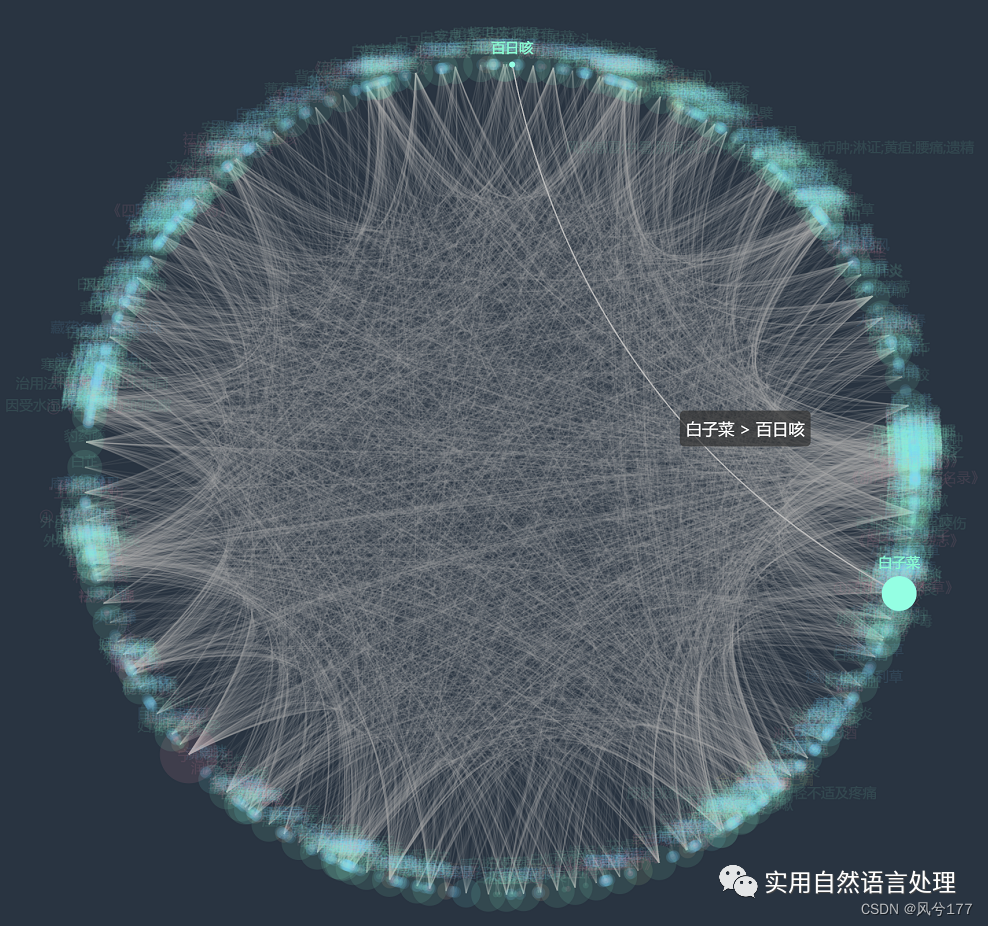

本文将基于pyecharts框架,对中药材知识图谱进行“力导图”和“环形分布”可视化,同时,对中药材地理分布、来源和别名关系进行分析与可视化。

2.2 中药材知识图谱可视化

前文自顶向下构建中药知识图谱初探已经介绍了中药材知识图谱的构建和neo4j可视化过程,接下来将对该图谱数据利用pyecharts进行可视化。

较多数据的知识图谱可视化效果